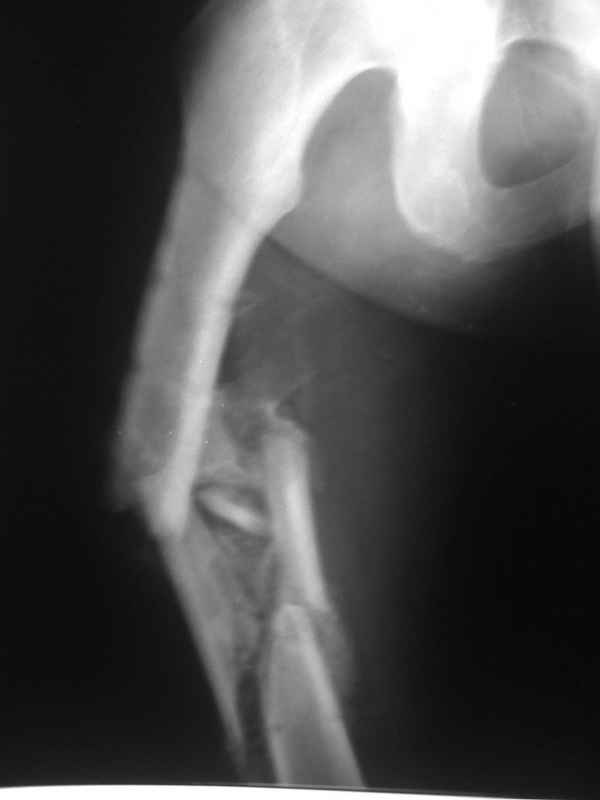

Пациент 39 лет. Травма в ДТП 2.5 месяца назад. Тяжелая сочетанная травма. ЗЧМТ. Тупая травма живота. Разрыв селезенки. Надрывы печени. Перелом бедра. При поступлении лапаротомия. Спленэктомия. Фиксация перелома бедра стержневым аппаратом. в последующем инфаркт мозга на фоне жировой эмболии. длительное нахождение на ИВЛ. Обширный пролежень в области крестца. и т.д.в настоящее время состояние больного стабилизировалось. активизирован на ходунках.имеется деформация бедра, укорочение 10 см. гранулирующий пролежень в области крестца. патологической подвижности в зоне перелома не отмечается.Оптимальные сроки проведения реконструктивной операции на бедре? Сейчас? Или после окончательного сращения?

А откуда такое укорочение взялось, 10см? По представленному фрагменту рентгенограммы понять трудно. В любом случае, если состояние пациента позволяет оперировать сейчас, зачем откладывать операцию до формирования монолитного сращения?

Конечно, снимки для планирования надо нормальные, не такой огрызок.

Можно закрыто мобилизовать отломки, наложить дистракционный аппарат, восстановить ось и длину, да и заштифтовать, на всякий случай с антибиотиковым цементным покрытием.